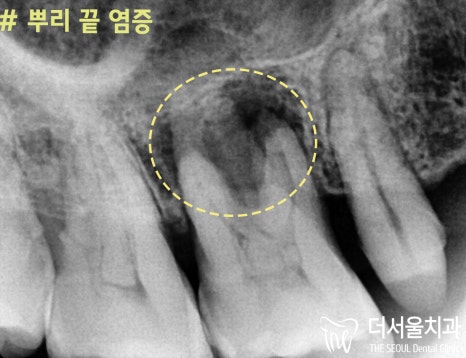

#16번: 심한 뿌리 끝 염증

#16번

대구치 부위를 발치 하고 나서

뿌리 끝 염증을 깨끗하게 긁어낼 수 있었습니다.